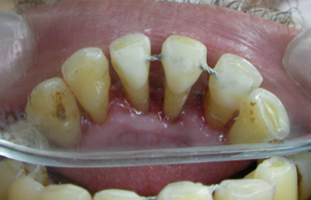

Splinting of teeth involve binding of loose or traumatized tooth to the adjacent firm teeth. This is like splinting a broken arm in a plaster, where the immobility forced on the loose tooth helps the periodontal tissue to heal. Post orthodontic treatment, sometimes a permanent splint is place on the lingual surface from canne to canine, if patient is not able to use retention plates.

Periodontally weak teeth: